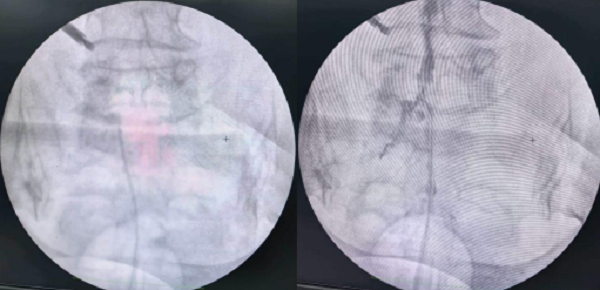

近日,玉溪市人民医院疼痛科采用椎间孔扩大成形术,成功为2名饱受腰腿痛困扰的高龄患者解除病痛,显著改善生活质量。

手术中,团队通过硬膜外神经松解+经皮椎间孔韧带切除的微创方式,精准松解神经粘连、解除神经压迫,创伤小、恢复快,术后患者疼痛即刻缓解,疗效确切。

其中一位患者为93岁高龄女性,长期受腰背部及双下肢疼痛折磨,严重影响日常生活。经检查确诊为多节段腰椎间盘突出、神经受压、腰椎重度退变。考虑患者年事已高、基础疾病较多,科室经充分评估讨论,为其量身制定椎间孔扩大成形微创手术方案,术后疼痛明显缓解。

另一位81岁女性患者,腰腿痛病史较长,在外院多次治疗效果不佳。入院后确诊为L4/5腰椎间盘突出伴腰椎管狭窄,且基础疾病多、心肺功能较差。经综合研判,团队为患者实施微创椎间孔扩大成形术,顺利解除神经压迫与粘连,患者术后恢复顺利,对治疗效果十分满意。